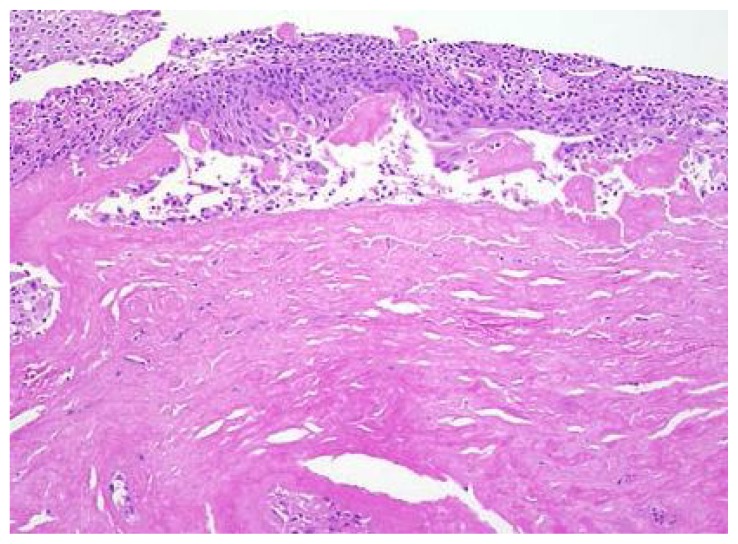

Figure 4.

Histopathology showing pink amorphous material in the lamina propria.